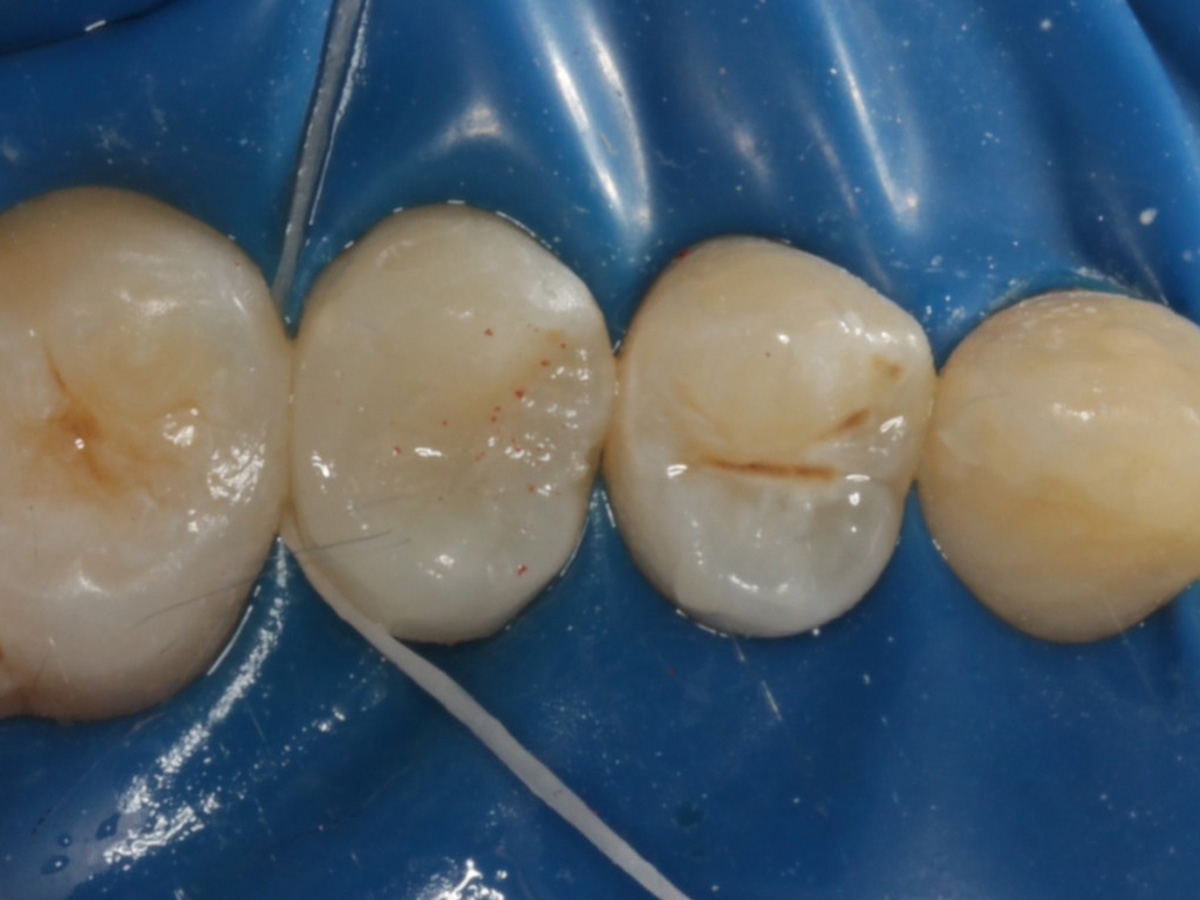

Abbildung 1

Approximalraumkaries an Zahn 25 distal